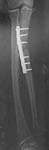

I bring the following case which is on-going and your thoughts would be of interest. 29yr old male left hand dominant Occupation: Chef six months ago presents initially with "night stick " with closed fracture to Left proximal ulnar shaft to hospital outside UK . This is treated with ORIF. This soon becomes infected and eventually the patient transfers back to United kingdom for an aggressive debridement (see films)

He is then put into an above elbow plaster and referred to our non union clinic. When seen now he is six months from initial injury unable to work and still wearing an above elbow POP . on exam out of POP: soft tissues fully healed no clinical infection no longer on antibiotics. wrist movements slight restricted but pain free pronation 10 degs supination 70 degrees elbow range 40 - 110 degrees pain free sensation normal Hand function normal except for Flexor pollicis longus not functioning 6 cm deficiency in ulna over to you for discussion.